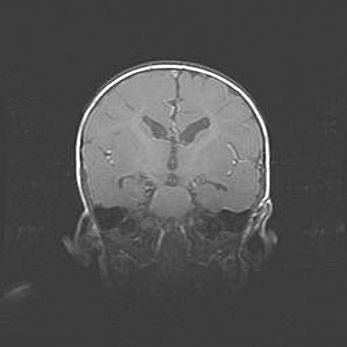

Наружная гидроцефалия с возможной атрофией височных областей.

Возраст: 28 дней

Вес: 3670 г

Пол: мужской

Окружность головы: 38 см

Срок гестации: 40 недель

Гидроцефалия головного мозга у новорожденных – это заболевание, которое характеризуется скоплением избыточного количества спинномозговой жидкости в желудочковой системе головного мозга в результате затруднения её перемещения от места выработки к месту поглощения в кровеносную систему или вследствие нарушения абсорбции. При открытой наружной форме гидроцефалии у новорожденных расширяются и переполняются субарахноидные пространства.

При нормотензивных  формах,  которые,  как  правило,  являются  следствием  перенесенных ишемических  повреждений  паренхимы  мозга,  возможно  сочетание микроцефалии  с нормотензивной гидроцефалией. В основе данных изменений лежит атрофия больших полушарий с преимущественной  локализацией  в  лобно-височных  областях.